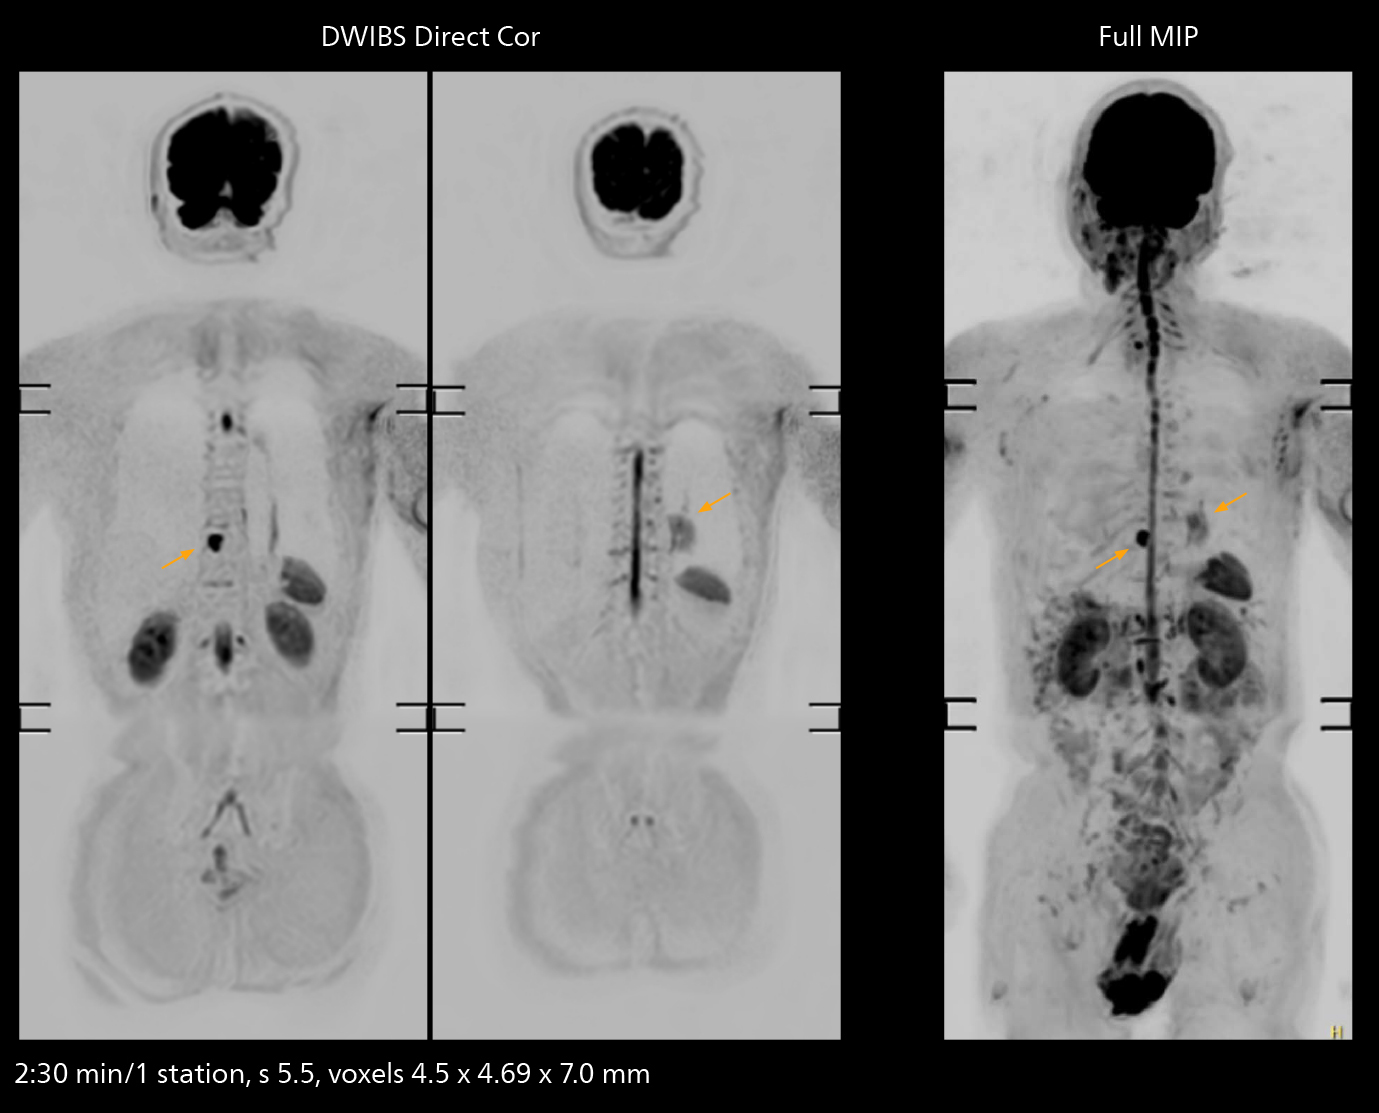

The high performance of the Vega HP gradients is particularly impressive in DWI. “The Vega HP gradients enable us to scan faster and use b-values as high as 2000, for example in prostate DWI and in DWIBS, which provides image quality that is remarkably improved over the previous system and we are able to more easily see lesions.”

The value of the Elition X gradients is also evident in DWIBS studies. “The fact that we can consistently obtain distortion‐free DWIBS while reducing imaging time at three coronal stations is excellent,” Dr. Makuuchi says. “In these patients, it’s also important that the application of Compressed SENSE to T2‐weighted, STIR and mDIXON sequences has no impact on the examination time of whole‐body imaging. As a result of the increased speed and higher image quality we realize, DWIBS studies have now become routine examinations.”

With SmartPath to Elition X the team can obtain excellent quality DWIBS imaging and reduce imaging time. Other sequences also fit in the examination slot. This case shows left paravertebral neurogenic tumor and Th10 vertebral hemangiomas.